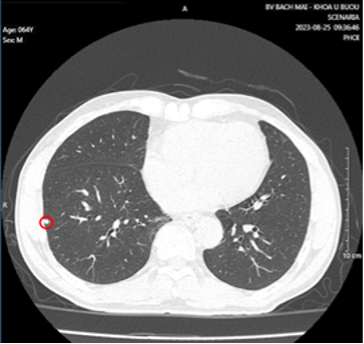

- Cắt lớp vi tính lồng ngực có tiêm thuốc cản quang:

Hình 2: Vài nốt đặc nhu mô phổi 2 bên, kích thước lớn nhất 5x6mm